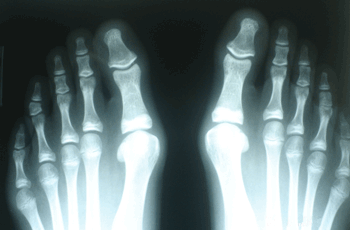

INDICACIONES

Hallux Valgus del Adolescente